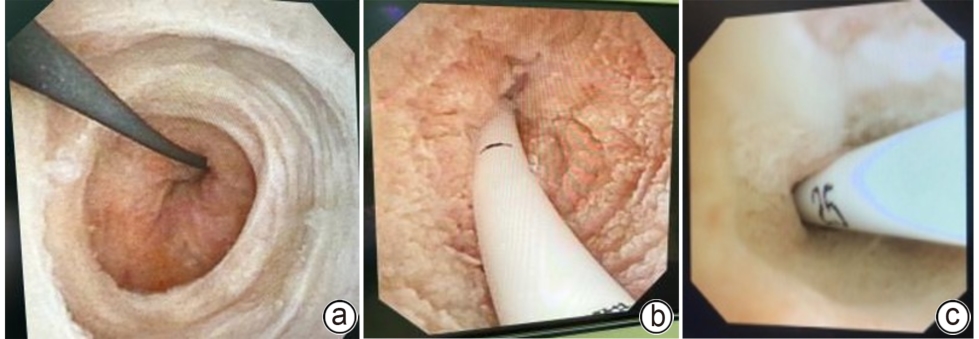

An excerpt of World Endoscopy Organization guidelines on endoscopic retrograde cholangiopancreatography biliary cannulation and sphincterotomy techniques (2025 edition)

Junlong LIN, Yunpeng HUA

2025, 41(10): 2009-2012. DOI: 10.12449/JCH251009

Abstract(143) HTML (35) PDF (579KB)(64)

Abstract:

There is still a lack of guidelines on biliary cannulation in recent years. The guidelines are an initiative of the World Endoscopy Organization (WEO) formulated by a panel of experts from Asia, Europe, and America. Through a systematic literature review and the application of the Grading of Recommendations Assessment, Development, and Evaluation methodology, the guidelines address clinical questions pertaining to four key domains, i.e., prevention of post-ERCP pancreatitis (PEP), bile duct cannulation techniques, sphincterotomy/papillary balloon dilation, and bile duct cannulation under special circumstances. Successful biliary cannulation and sphincterotomy are cornerstones of ERCP and are indispensable for almost all therapeutic and advanced diagnostic procedures; however, adverse events, especially PEP, may occur frequently and affect the prognosis of patients. A high success rate of bile duct cannulation and a low incidence rate of PEP are quality indicators for ERCP and should be the goal of all endoscopists. The guidelines aim to provide clinical practice recommendations applicable worldwide, regardless of resources and expertise. The guidelines cover the preoperative, intraoperative, and postoperative management of ERCP, including the measures to reduce the risk of PEP, the technique for an initial biliary cannulation attempt, options for cannulation in case of difficult biliary access, alternatives to ERCP in case of failure (under the guidance of percutaneous and endoscopic ultrasound), and biliary access in altered anatomy (periampullary diverticulum and postsurgical anatomy) and in the presence of duodenal stenosis.